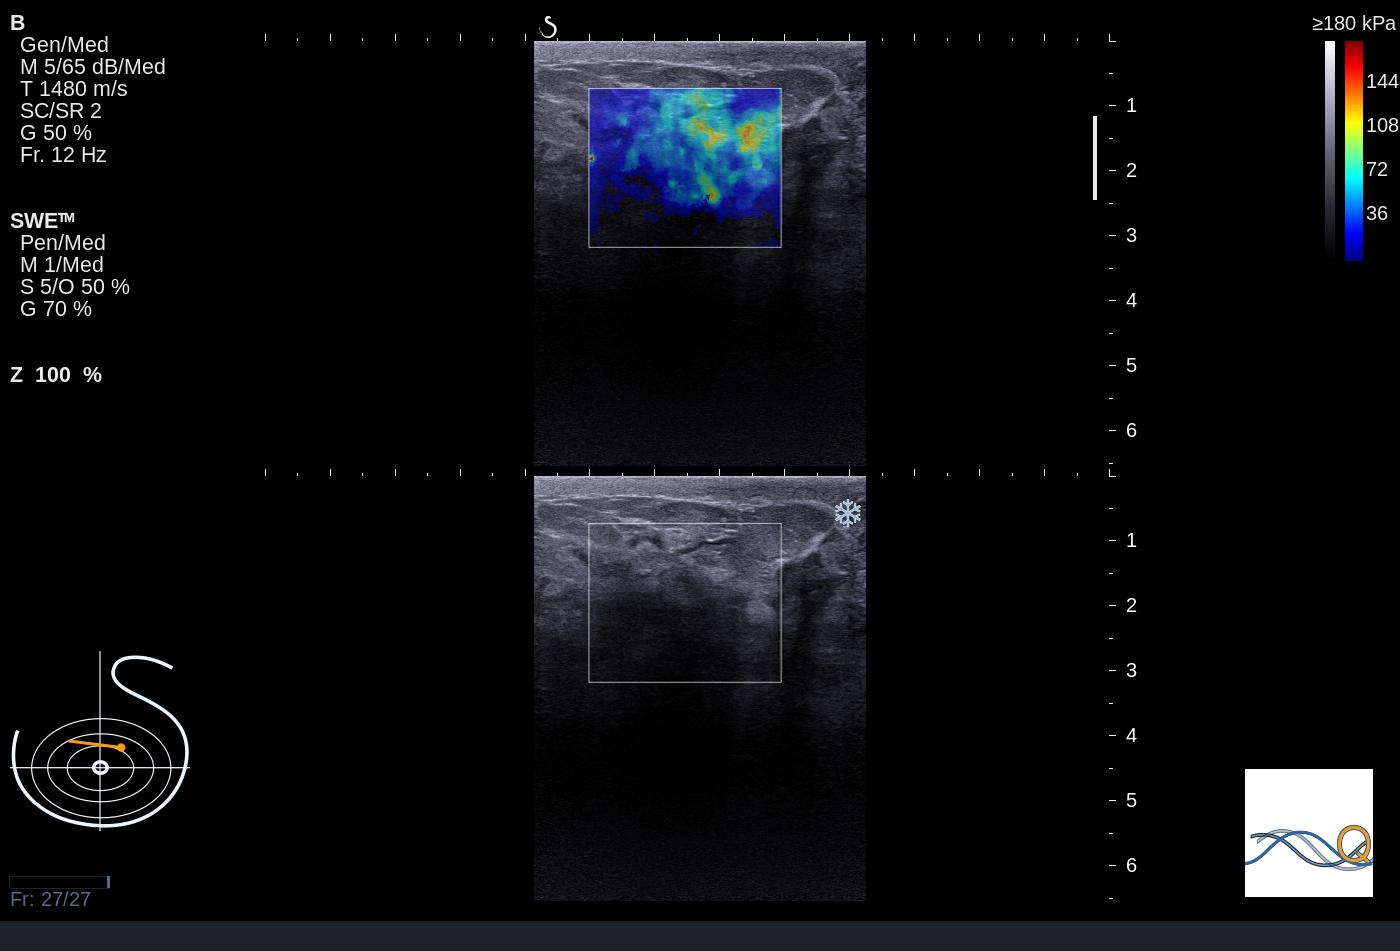

ich hab da ein Ultraschallbild in dem sich ein Elastogramm (Rahmen) befindet. Das US-Bild ist ein RGB-Bild und der Rahmen ist weiß. Nun möchte ich den Start des Rahmens herausfinden.

im Anhang befindet sich eine Beispielaufnahme.

Also der 'Start vom Rahmen' ist die obere Kante des Rechtecks in der Ultraschallaufnahme.

| Beschreibung: |

ExportedDCM20131121134703_1 Kopie.jpg |